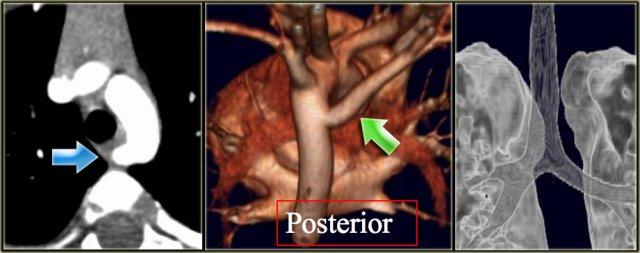

Right Arch with Aberrant left subclavian

The Right Aortic Arch with an aberrant left subclavian is an obstructing arch anomaly.

The first branch of the aorta is the left common carotid, followed by the right subclavian artery and the left common carotid.

This also is a true ring.

The ligamentum ductus arteriosus between the arch at the level of the left subclavian artery and the left pumonary artery completes the ring.

If this ligament is very short, there will be a lot of compression.

On the left a patient with a right arch with an aberrant left subclavian (indicated by the yellow arrow).

Scroll through the images on the left.

Again you have to realize that the axial CT-images have a ‘view from feet’.

Which vessels are indicated by the yellow and green arrow?

There is a right arch and the left subclavian artery is the last branch of the aortic arch, indicating that this is an aberrant left subclavian.

Medially to the left subclavian artery we see the left common carotid, that originates from the right side and has an oblique course to the left.

The yellow arrow indicates the azygos vein.

The green arrow indicates the left superior intercostal vein, a normal variant, that we will discuss later.

Same patient.

Posterior oblique view of volume rendered image to show the aberrant left subclavian artery.

In a mirror type right arch, the left subclavian is the first brach and forms the left innominate together with the left common carotid.

On the left images of a symptomatic child.

On the axial image there is a right arch with the left subclavian artery that comes off on the posterior side and runs behind the trachea and the esophagus.

The compression of the trachea is demonstrated on the volume rendered view.